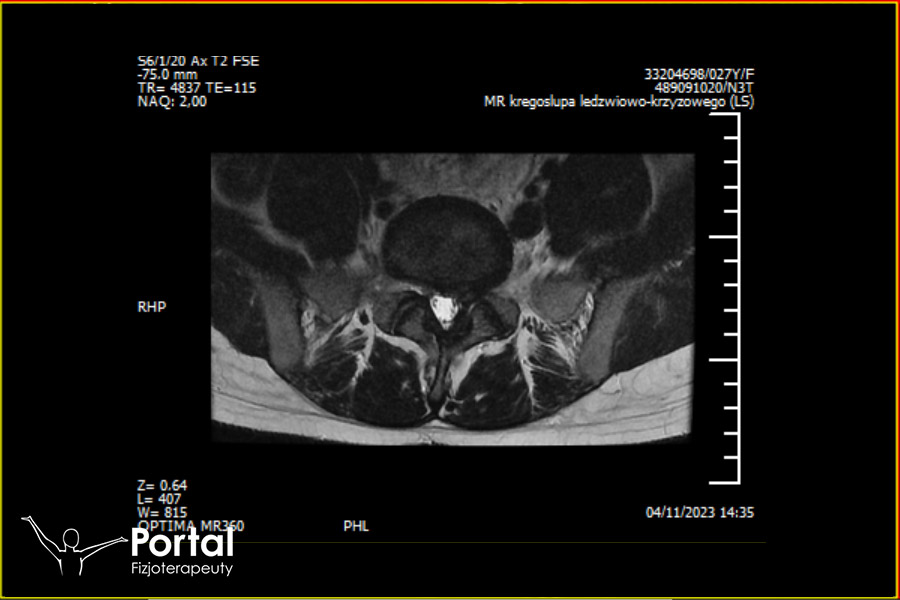

Wypadnięcie jądra miażdżystego

Wypadnięcie jądra miażdżystego to powszechnie stosowana nazwa odnosząca się do dyskopatii i często wskazująca na przepuklinę jądra miażdżystego. Jest to […]